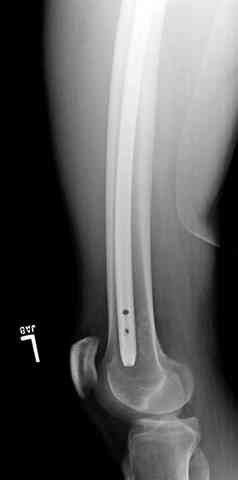

Здесь представлены несколько случаев лечения огнестрельного перелома

3 сегментарный перелом бедра с переломом Хоффа фрагментом, сделано из минимального доступа